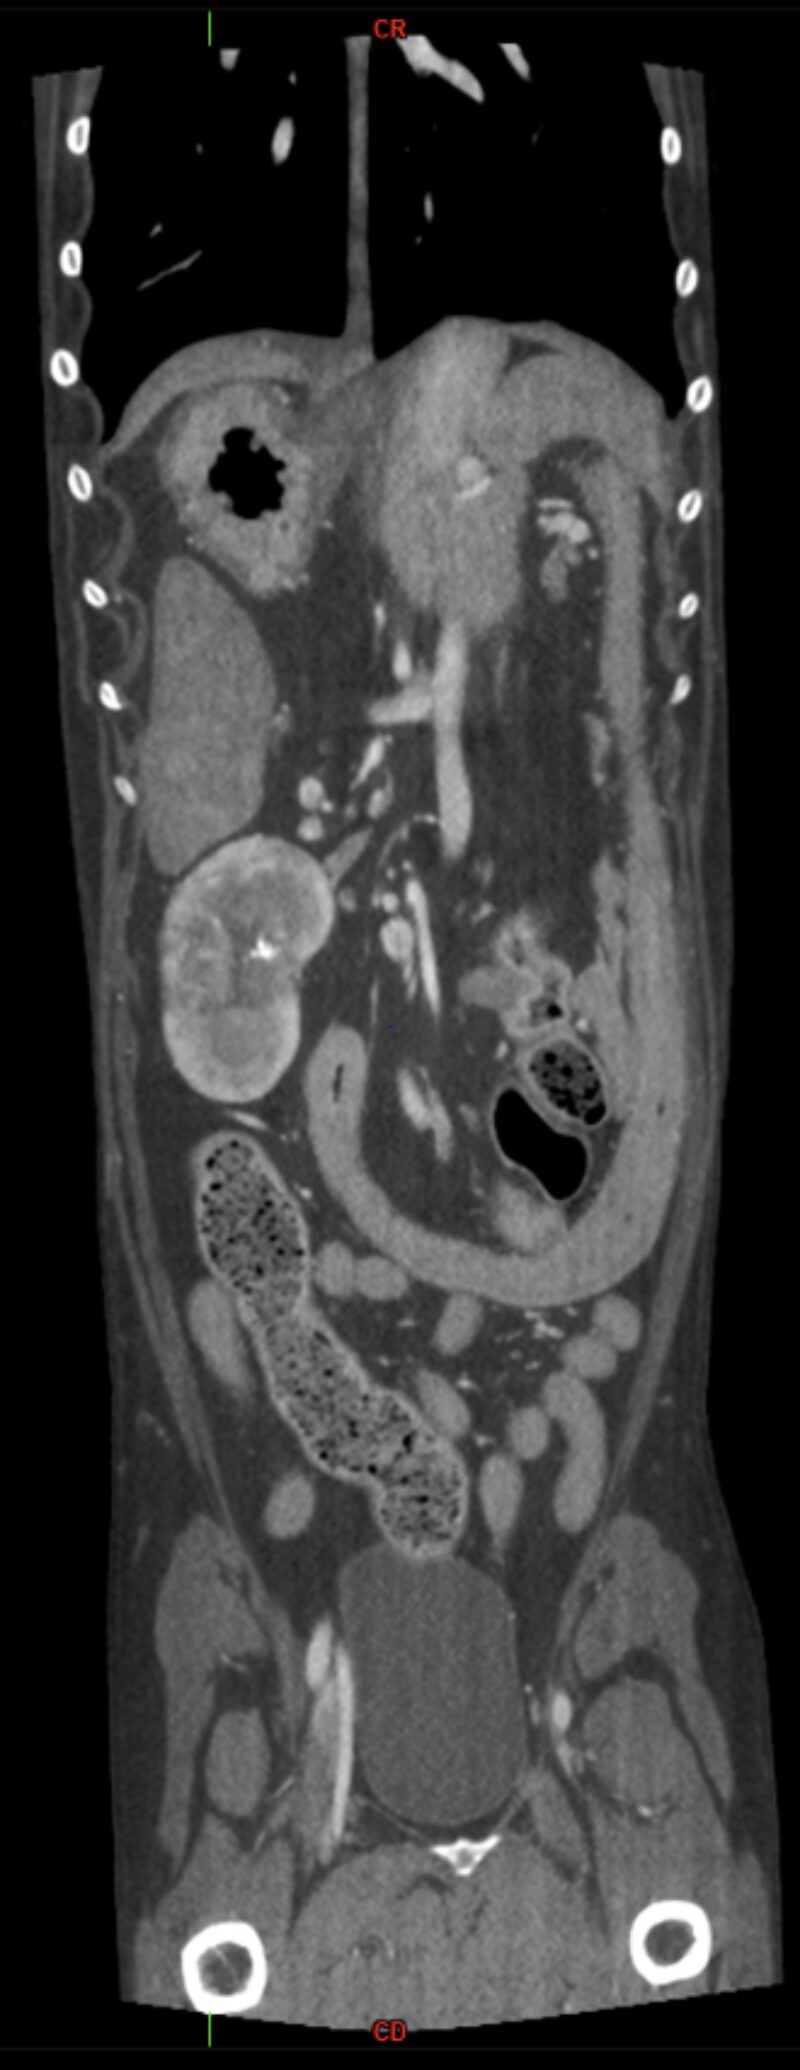

Abdomen: Ein wesentlicher Schwerpunkt unserer klinischen Arbeit liegt im Abdomen. Neben der Darstellung abdominaler Tumoren und struktureller Organveränderungen konnten auch Gefäßanomalien wie portosystemische Shunts erfolgreich dargestellt werden. Für viele klar definierte Fragestellungen stellt das CBCT eine praktikable und diagnostisch wertvolle Alternative zum MSCT dar (Abb. 5 & 6).